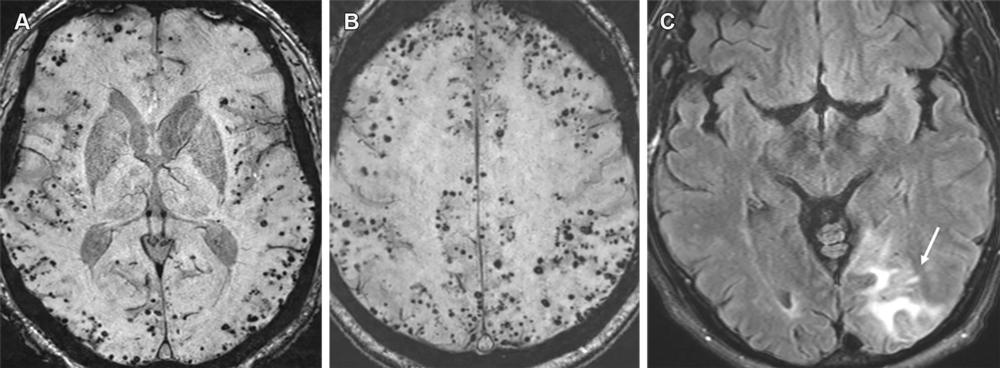

Figure 11. Moderate ARIA-H (microhemorrhage) in a 70-year-old man with no clinical symptoms receiving aducanumab therapy. Baseline axial GRE MR image (A) was unremarkable, with the development of seven new microhemorrhages (arrows in B) depicted on the follow-up image (B) and magnified inset image obtained 7 weeks after the target dose. Therapy was suspended for few weeks and was resumed following documentation of stable findings at follow-up MRI. It is important to maintain consistency in the sequence type (T2*-weighted GRE) and scanner type (all examinations performed with same strengths) as technical factors can result in miscounting of the number of microhemorrhages.

High-res (TIF) version